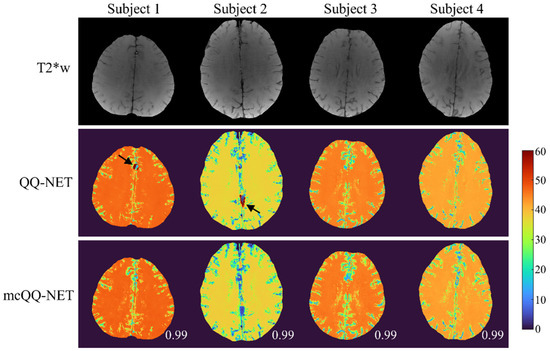

- Cho, J.; Zhang, J.; Spincemaille, P.; Zhang, H.; Hubertus, S.; Wen, Y.; Jafari, R.; Zhang, S.; Nguyen, T.D.; Dimov, A.V.; et al. QQ-NET—Using deep learning to solve quantitative susceptibility mapping and quantitative blood oxygen level dependent magnitude (QSM + qBOLD or QQ) based oxygen extraction fraction (OEF) mapping. Magn. Reson. Med. 2021, 87, 1583–1594. [Google Scholar] [CrossRef]